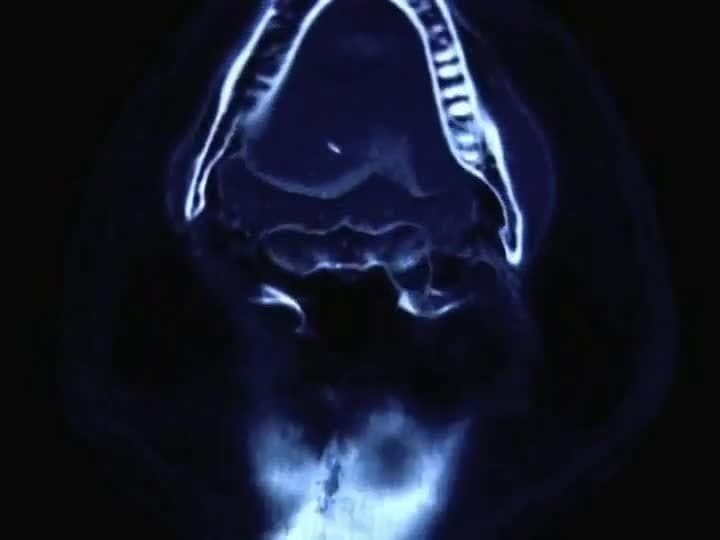

Virtual Archaeology: How Computer Tomography Changed Archaeology

How are the same processes used for Egyptian mummies? Virtual Archaeology, Part 4